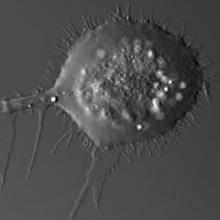

Cell fusion is a process by which two cells ('parent cells') fuse to create a hybrid cell. When the two parent cells fuse, their genetic contents (blueprints) are combined, possibly giving the hybrid new abilities.

There are times when cell fusion is a normal event, such as fertilization, and … more